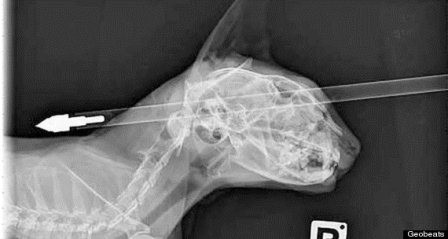

| Chú mèo Moo Moo bị mũi tên bắn xuyên qua đầu. |

Tờ Stuff.co.nz đưa tin, chú mèo có tên Moo Moo, 6 tuổi, đã bị thương khi bị một thanh niên 18 tuổi tập bắn nỏ vô tình bắn trúng. Sau khi bị bắn mũi tên vào đầu, Moo Moo đã cố gắng chạy trốn vào trong nhà, nhưng không thể vào được do mũi tên quá dài và bị vướng các vật thể xung quanh.

Chủ nhân của Moo Moo là cô Ferrari đã nhanh chóng đưa con mèo đến bác sĩ thú y để lấy mũi tên ra với hi vọng có thể cứu sống Moo Moo. Bác sĩ Jonathan Bray - người đã khám và điều trị cho Moo Moo - lúc đầu cũng rất sốc khi ông nhìn thấy mũi tên xuyên qua đầu. Tuy nhiên sau đó bác sĩ phát hiện thấy vết thương do mũi tên gây ra không quá nghiêm trọng và có thể cứu sống con mèo.

| Mặc dù bị bắn xuyên qua đầu nhưng may mắn không ảnh hưởng đến tính mạng. |

Chia sẻ với tờ 3News.co.nz, bác sĩ Jonathan Bray cho biết: “Nó bị thương nhẹ một ở phần mũi và hốc mắt, nhưng cũng có thể nói nó là chú mèo may mắn. Tốc độ của mũi tên bắn vào đầu là cực kỳ mạnh, và Moo Moo là một chú mèo can đảm. Tình trạng sức khỏe của Moo Moo hiện khá tốt, vết thương đang dần bình phục và không có tác động xấu về lâu dài”.